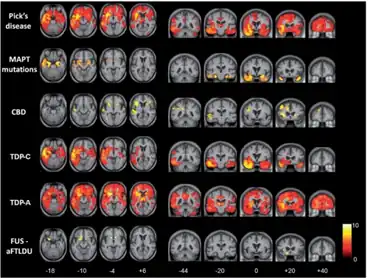

| Neuropathologic analysis of brain tissue from FTLD-TDP patients. Ubiquitin immunohistochemistry in cases of familial FTLD-TDP demonstrates staining of (a) neurites and neuronal cytoplasmic inclusions in the superficial cerebral neocortex, (b) neuronal cytoplasmic inclusions in hippocampal dentate granule cells, and (c) neuronal intranuclear inclusions in the cerebral neocortex (arrows). Scale bar; (a) and (b) 40 μm, (c) 25 μm, insert 6 μm. | |